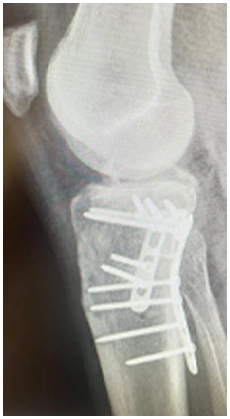

As osteotomias são procedimentos cirúrgicos que envolvem o corte e reposicionamento dos ossos ao redor da articulação do joelho para corrigir deformidades angulares, como a osteoartrose em estágio inicial ou instabilidade ligamentar. Esse procedimento visa redistribuir as forças na articulação do joelho e aliviar a pressão sobre as áreas danificadas da cartilagem.